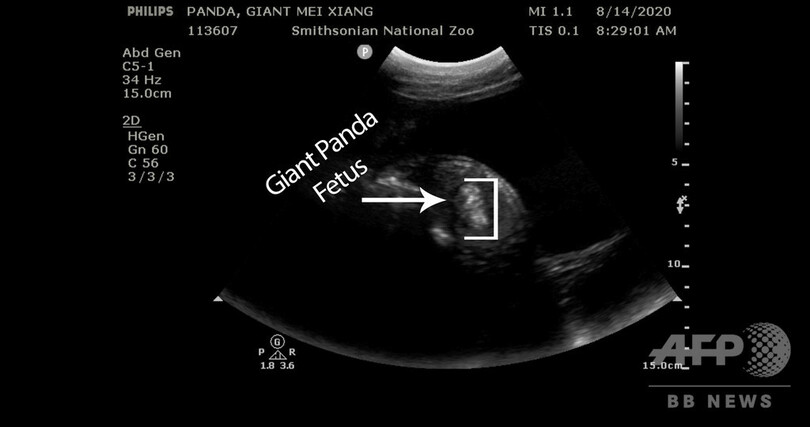

【8月18日 AFP】米首都ワシントンにあるスミソニアン国立動物園(Smithsonian's National Zoo)は17日、22歳の雌のジャイアントパンダ、メイシャン(美香、Mei Xiang)が妊娠し、数日以内に出産する可能性があると発表した。

発表によると、超音波による診断で獣医師らが胎児を発見したという。